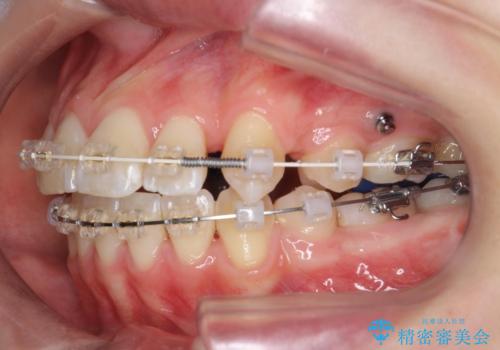

- 矯正装置

- ワイヤー矯正

- 2年8ヶ月

- 10-30回

前歯の角度を改善するために小臼歯4本の抜歯を行いワイヤー マルチブラケットを用いて、しっかりと前歯の角度を改善する治療計画としました。